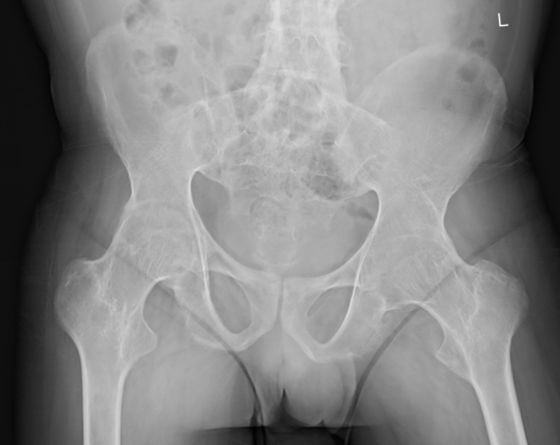

关节置换的手术时机至关重要。早期手术有利于降低手术风险及难度、尽早改善关节功能、提高患者生存质量、减少远期并发症的发生。关节置换治疗AS的适应症:1.髋膝关节强直、关节疼痛及活动受限、伴有结构破坏的X线征象;2.非手术治疗无效;3.评估患者身体可耐受手术创伤。术后康复重点在于提高肌肉力量、改善关节活动、控制疼痛、提高运动感觉的协调能力。提倡早期、积极的主动训练。

图:强直性脊柱炎伴轻度髋关节结构破坏改变